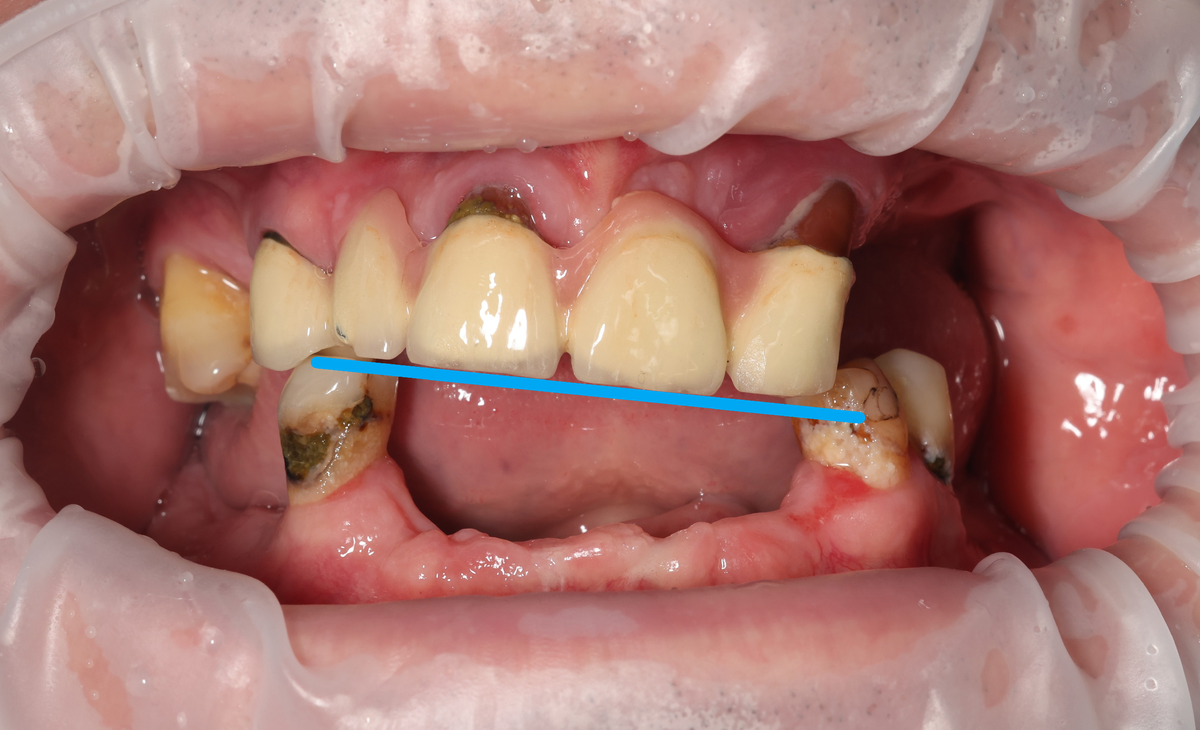

Особенность - зубы верхней челюсти (с коронками) из-за отсутствия зубов на нижней челюсти и пародонтита выползли из кости, покосились забором:

Мост уполз

Клык (зуб 3.3) ни туда, ни сюда. Получалась какая-то несуразица.

Варианта для исправления 2:

• делать кривой нижний протез;

• выравнивать (пилить) зубы верхнего моста.

Выбрали точить верхние зубы - потому что их будем удалять через некоторое время, устанавливая такой же тотал, как и снизу. Логично в такой ситуации не клепать неликвидный низ, а сделать его полноценным.